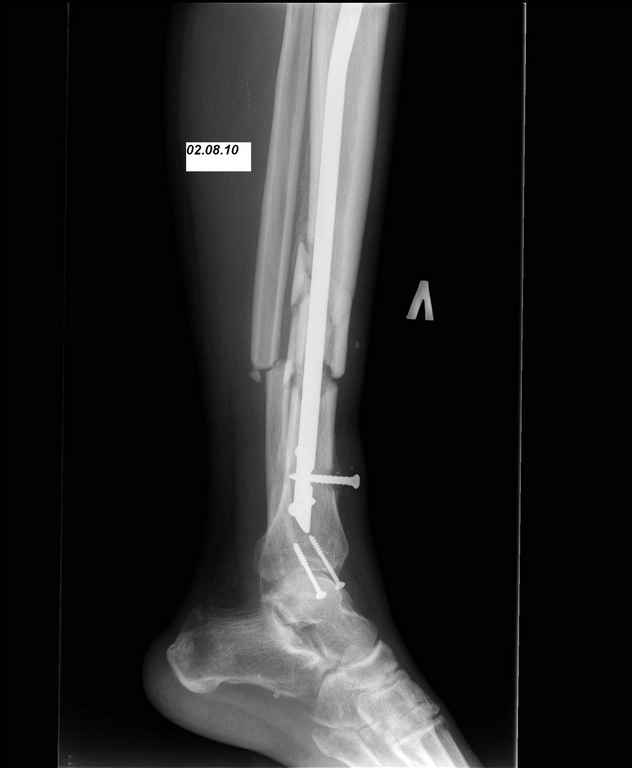

И вот опять объявился. Снимки и фотографии в приложении(первичные потеряны). Около 1 месяца назад появились боли в области нижней трети голени в проекции дистальных блокирующих винтов, передвигался с нагрузкой 50% (сам для себя так решил, сам себе разрешил). Путешествовал по Волгоградской области, обратился к травматологу, со слов перевязывали, лечили антибиотиками. Лучше не стало. Вернулся домой.

Вчера госпитализирован в отделение. Локально умеренный отек, кожная температуа не повышена. По передней поверхности в области дистального блокируюшего винта свищ, скудное гнойное отделяемое, винт удален на перевязке зажимом. «Старый» свищ не функционирует. Взят бак. посев, ждем результат.

Возможности и рассматриваемые варианты дальнейшего лечения: 1. удаление штифта, промывное дренирование, ЧКДО. Ждать сращения. 2. удаление штифта, ДРУ (по Челнокову А.Н.), понаблюдать несколько дней+антибиотики(в\в/в\м, перевязки), временно спейсер?, затем БИОС штифтом с АБ покрытием (есть штифты Synthes, Sanatmetal; по нашему мнению самый отпимальный вариант, НО более взрослые коллеги не поддерживает наших «новаторских» предложений, поэтому опыт штифтования с АБ покрытием небольшой). Варианты типа удалить штифт+гипс или вытяжение не рассматриваем. Подскажите, пожалуйста, какой вариант наиболее предпочтительней. И терзает вопрос, что привело к нагноению/остеомиелиту? Нестабильность? В настоящее время с пациентом проведена беседа, настроен на лечение, регулярное наблюдение, выполнение рекомендаций. Ждем Ваших советов и комментариев. Заранее спасибо.